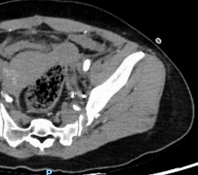

患者因外伤来诊时,CT检查提示骨盆骨折伴盆腔血肿,同时意外发现Stanford B型主动脉夹层——这是两个都可能危及生命的急症。面对如此复杂情况,介入科团队第一时间行动。

在患者生命体征尚平稳但潜在风险极高的情况下,我们结合CT增强检查及三维重建结果,考虑盆腔存在活动性出血,果断通过绿色通道经股动脉穿刺行盆腔动脉造影,竟发现至少3条动脉存在损伤情况。随即迅速以导丝导管结合技术超选择插管至出血责任动脉并成功实施栓塞术。相对传统开腹探查手术,这项微创介入技术不仅大大节省了宝贵的抢救时间,更是避免了开腹手术的创伤,用最小的代价稳定了患者的生命体征,为后续治疗赢得了宝贵时间。